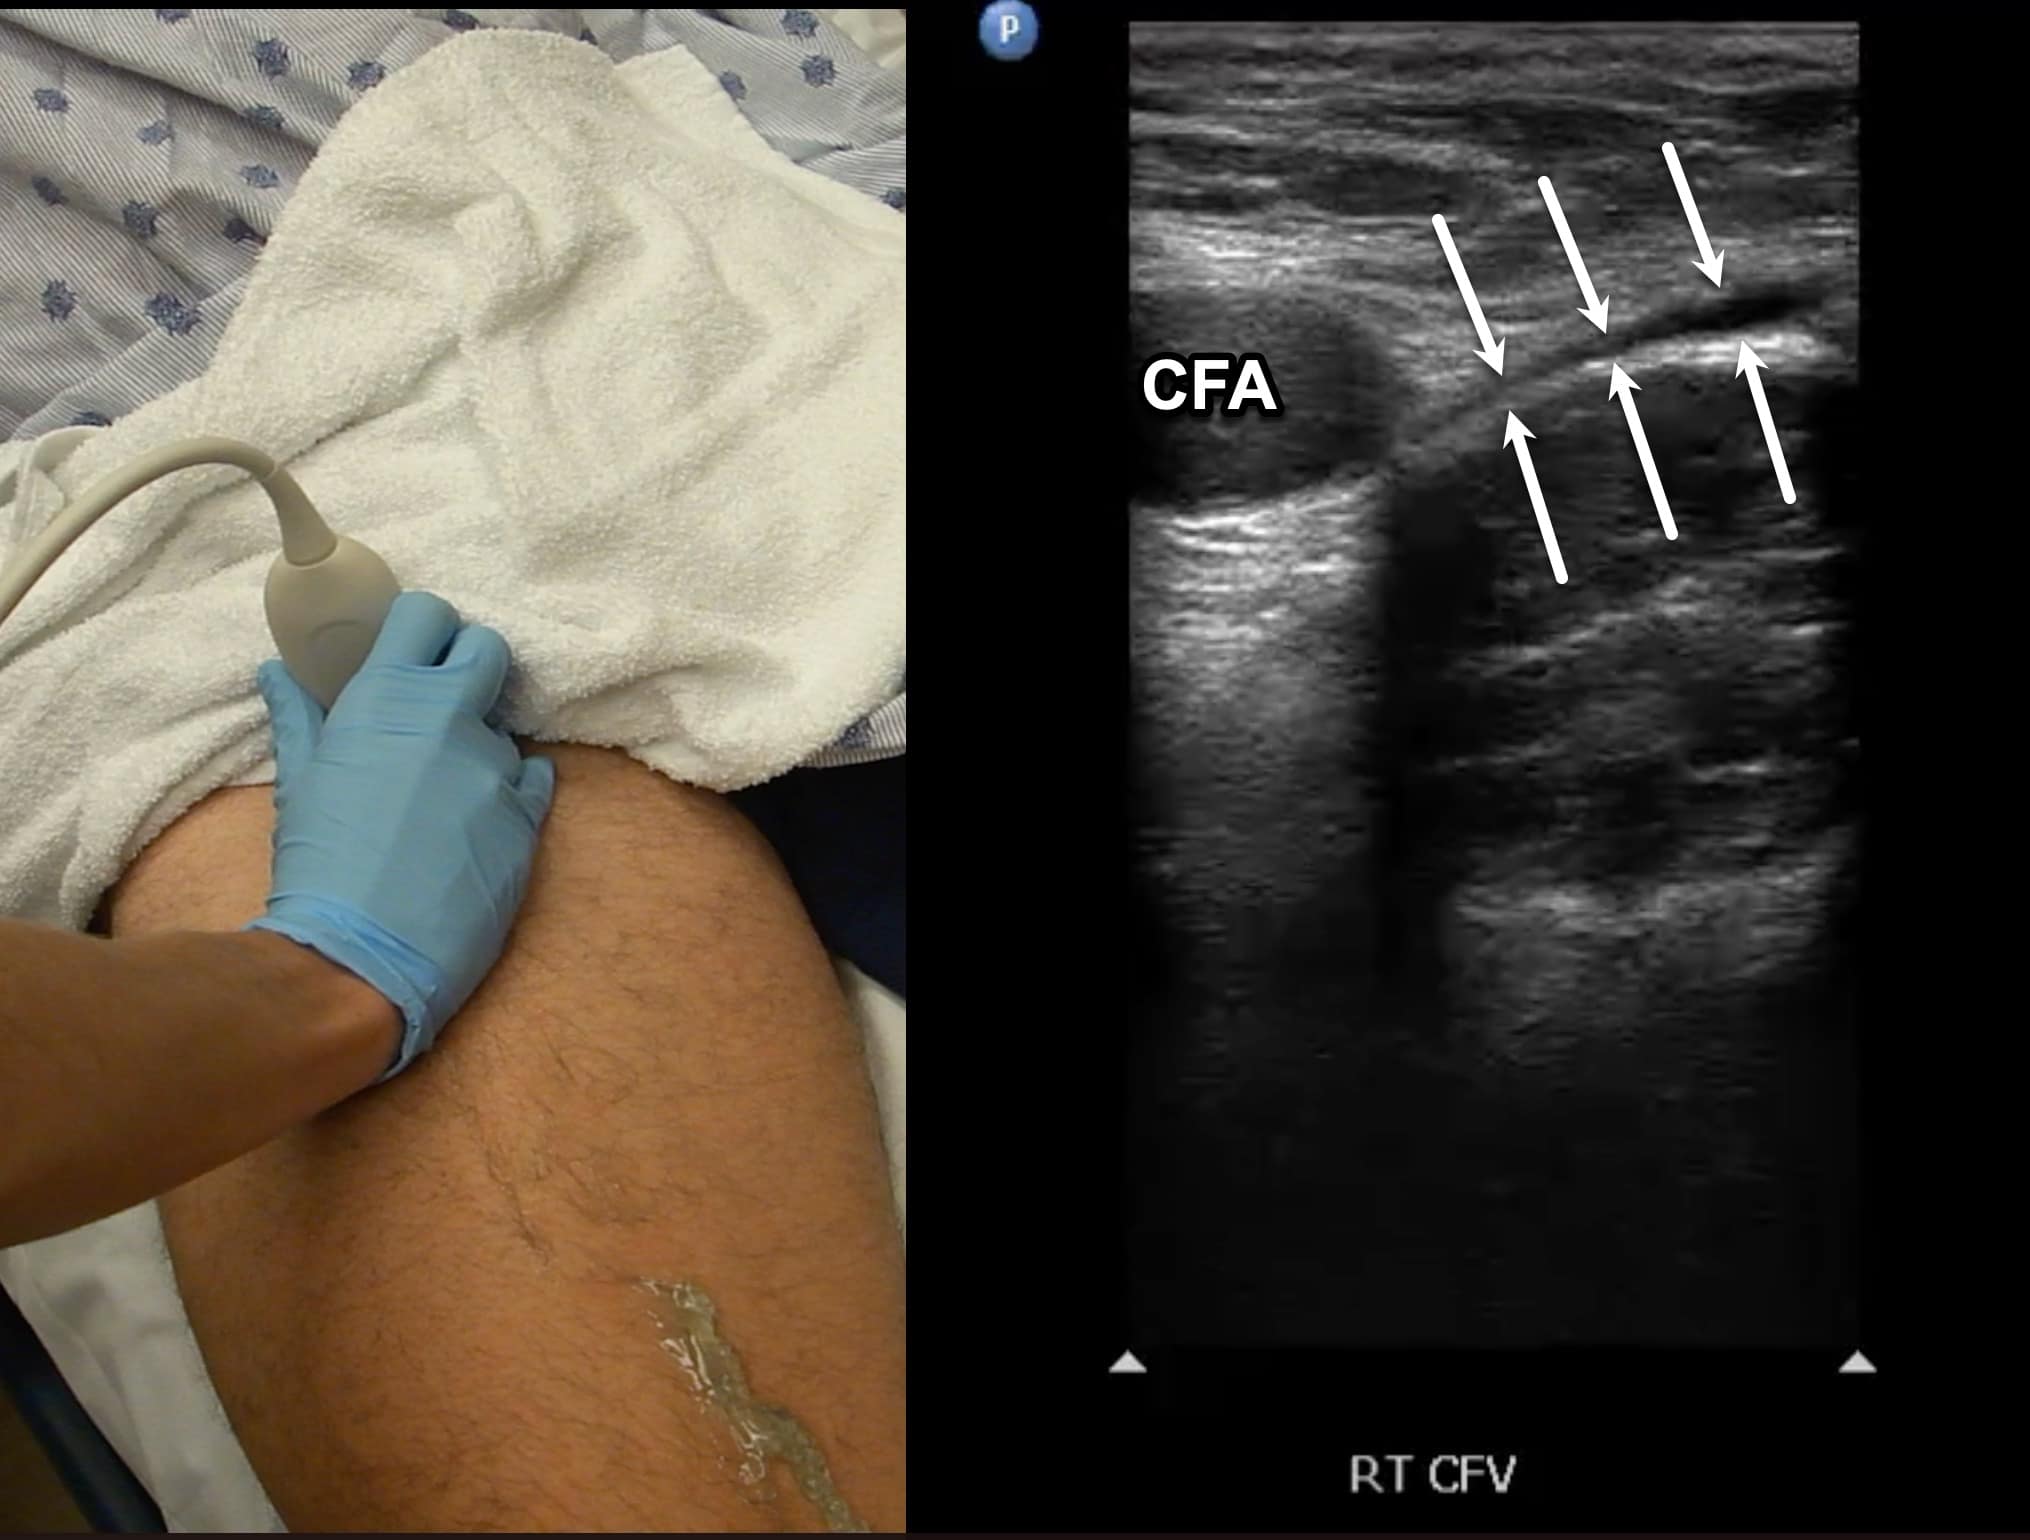

Due to its location in the pelvis, the EIV can be difficult to visualize, so the proximal protocol begins with the transducer in the transverse position high in the groin, just distal to the inguinal ligament with the CFV at the saphenous vein (SV) branch point visualized (Figure 3). A normal vein will be anechoic and easily compressible (Figure 4). Compression should be performed with the transducer transverse to the vein with compression being directed in an anterior-posterior direction. Compression should not be performed in a longitudinal plane to the vein since false-positive results can occur from “side-walling” and sliding off the vein, which can appear sonographically as a true compression. Tenting of the artery means that more than enough pressure has been applied.

Figure 4. Split screen demonstrating compression of the common femoral vein (CFV) (between arrows) with transducer position shown. Note the common femoral artery (CFA) lateral to the CFV.